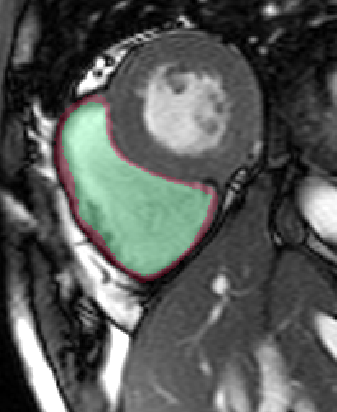

Table 2 summarizes the results of our method for RV segmentation in terms of image-based metrics. The results show that the algorithm performs better at ED than ES. This can be explained by the fact that the image quality is higher at ED than at ES. By analyzing the DM and HD on a slice-basis, it can be seen that the proposed method has a high performance on basal slices, with an average and . However, the segmentations on apical slices are of lower quality affecting the overall DM and HD scores. Figure 3 shows segmentation results in six different cases obtained from the challenge that illustrate the differences between basal and apical segmentations.

The results show that the method perform well on average but there are some cases in which it fails. In particular, our method has a very high performance on the basal slices, whereas the scores obtained for apical slices are lower (Figure 3). These can be explained by two factors: 1) The image quality at the apical slices is rather low. As the registration, the atlas ranking and the label fusion are intensity-based, poor image quality can affect the results, and 2) the regions to be segmented at the apical slices are rather small, which implies that the atlases’ masks are also small at these slices. When the masks are used in the registration process to supress undesired structures, the remaining information is insufficient, causing the intensity-based registration, rigid or non-rigid, to fail.

In conclusion, we have presented a fully automatic segmentation method applied to the extraction of RV epicardium and endocardium. The results show that the method is in average succesful in the segmentation results. The segmentations obtained in the basal slices are of very high quality, whereas the results in the apical ones are less good mainly because the registration stage fails to properly align the atlases with the unseen image.